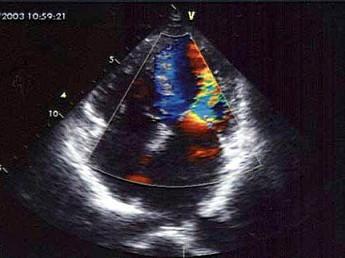

某患者舒张期二尖瓣口心动图所示,提示?(?)A.二尖瓣狭窄B.二尖瓣关闭不全C.二尖瓣脱垂D.正常声像图E.二尖瓣赘生物

选项 A.二尖瓣狭窄 B.二尖瓣关闭不全 C.二尖瓣脱垂 D.正常声像图 E.二尖瓣赘生物

答案 A